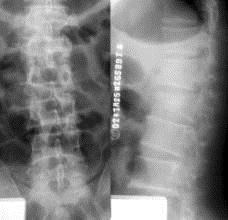

病历摘要: 患者×××,男性,21岁,不慎从3米高处坠落,双足着地,出现双足跟肿胀疼痛,腰痛不能站立。查体:腰1棘突有压痛和叩击痛,双足足跟部肿胀,触痛(...

问题 病历摘要: 患者×××,男性,21岁,不慎从3米高处坠落,双足着地,出现双足跟肿胀疼痛,腰痛不能站立。查体:腰1棘突有压痛和叩击痛,双足足跟部肿胀,触痛(+),双下肢感觉正常,双足伸足母、伸趾正常,双膝关节伸屈正常。 按照Frankel分级,脊髓损害的分组以下叙述正确的是: